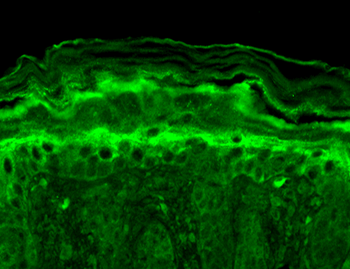

AM, ICC, IF, IHC, WB

应用稀释比例:WB (1:1000), IHC-P (1:1000), ICC/IF (1:100)

应用注释:1 µg/ml of SMC-323 was sufficient for detection of Slo2.2 in 10 µg of rat brain lysate by colorimetric immunoblot analysis using Goat anti-mouse IgG:HRP as the secondary antibody.